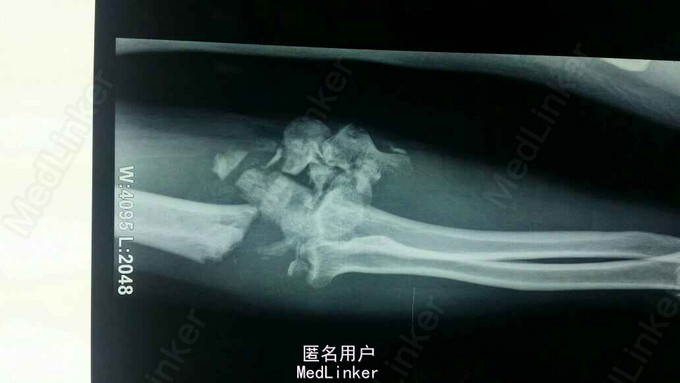

全身多发骨折,右肘关节粉碎性骨折。

对症治疗,消肿后行切开钢板内固定及外固定架固定术。